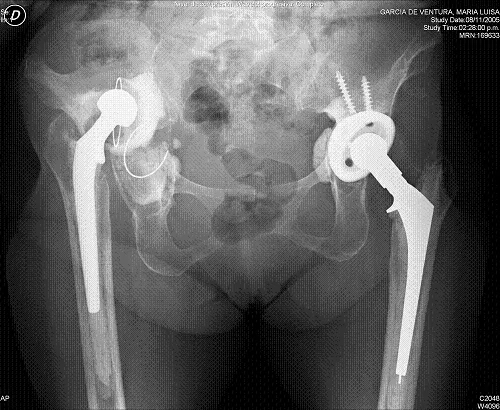

The head and femoral neck resection technique was described by Girdlestone in 1920 as a palliative treatment in patients with hip tuberculosis. This name is still used today to designate the removal of hip prostheses with cement and the regularization of the proximal portion of the remaining femur, when removal is required.

The complications that most frequently force this surgery are hip infections which, despite having decreased their incidence from 9.5% of the first prostheses of the sixties to values between 0.6% and 2.3% of the nineties, are a serious medical and economic problem. Other less frequent complications, but which may also require a Girdlestone intervention, are periprosthetic fractures, recurrent dislocations or the need for multiple hip arthroplasty replacements in poor quality bone. In these cases it remains a valid option to try to alleviate pain or improve the functional situation of patients.

The treatment of choice in an infected prosthesis is two-stage replacement; surgical cleaning of all elements, including cement; antibiotic treatment for a variable period depending on the germ and, subsequently, placement of a new prosthesis. However, in elderly patients with a poor clinical situation this alternative may involve more risks than benefits.